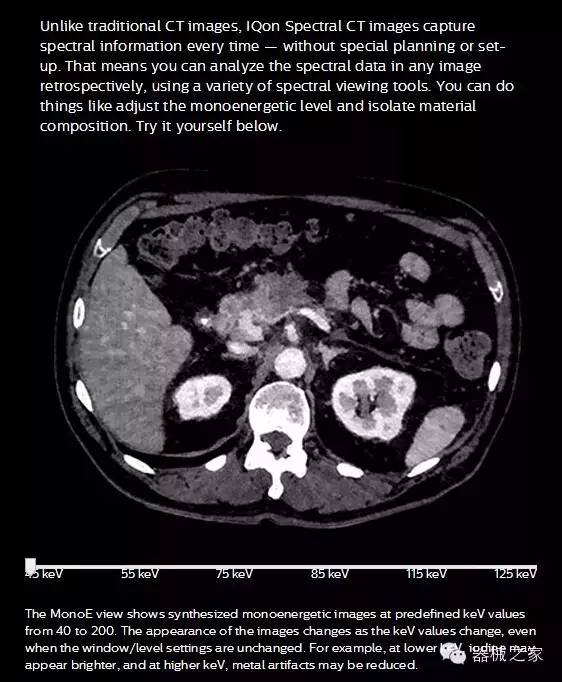

IQon光譜CT能夠按照需求提供光譜量化和工具,并能通過簡(jiǎn)單工作流程、在低劑量下對(duì)結(jié)構(gòu)進(jìn)行定性分析

IQon光譜CT -- 是業(yè)界首臺(tái)以探測(cè)器為成像基礎(chǔ)的光譜CT,它可以在單次常規(guī)掃描下獲得傳統(tǒng)解剖影像及光譜功能影像。不僅可以提供精準(zhǔn)的診斷信息,還可簡(jiǎn)化工作流程、在低劑量下完成定量與定性分析。